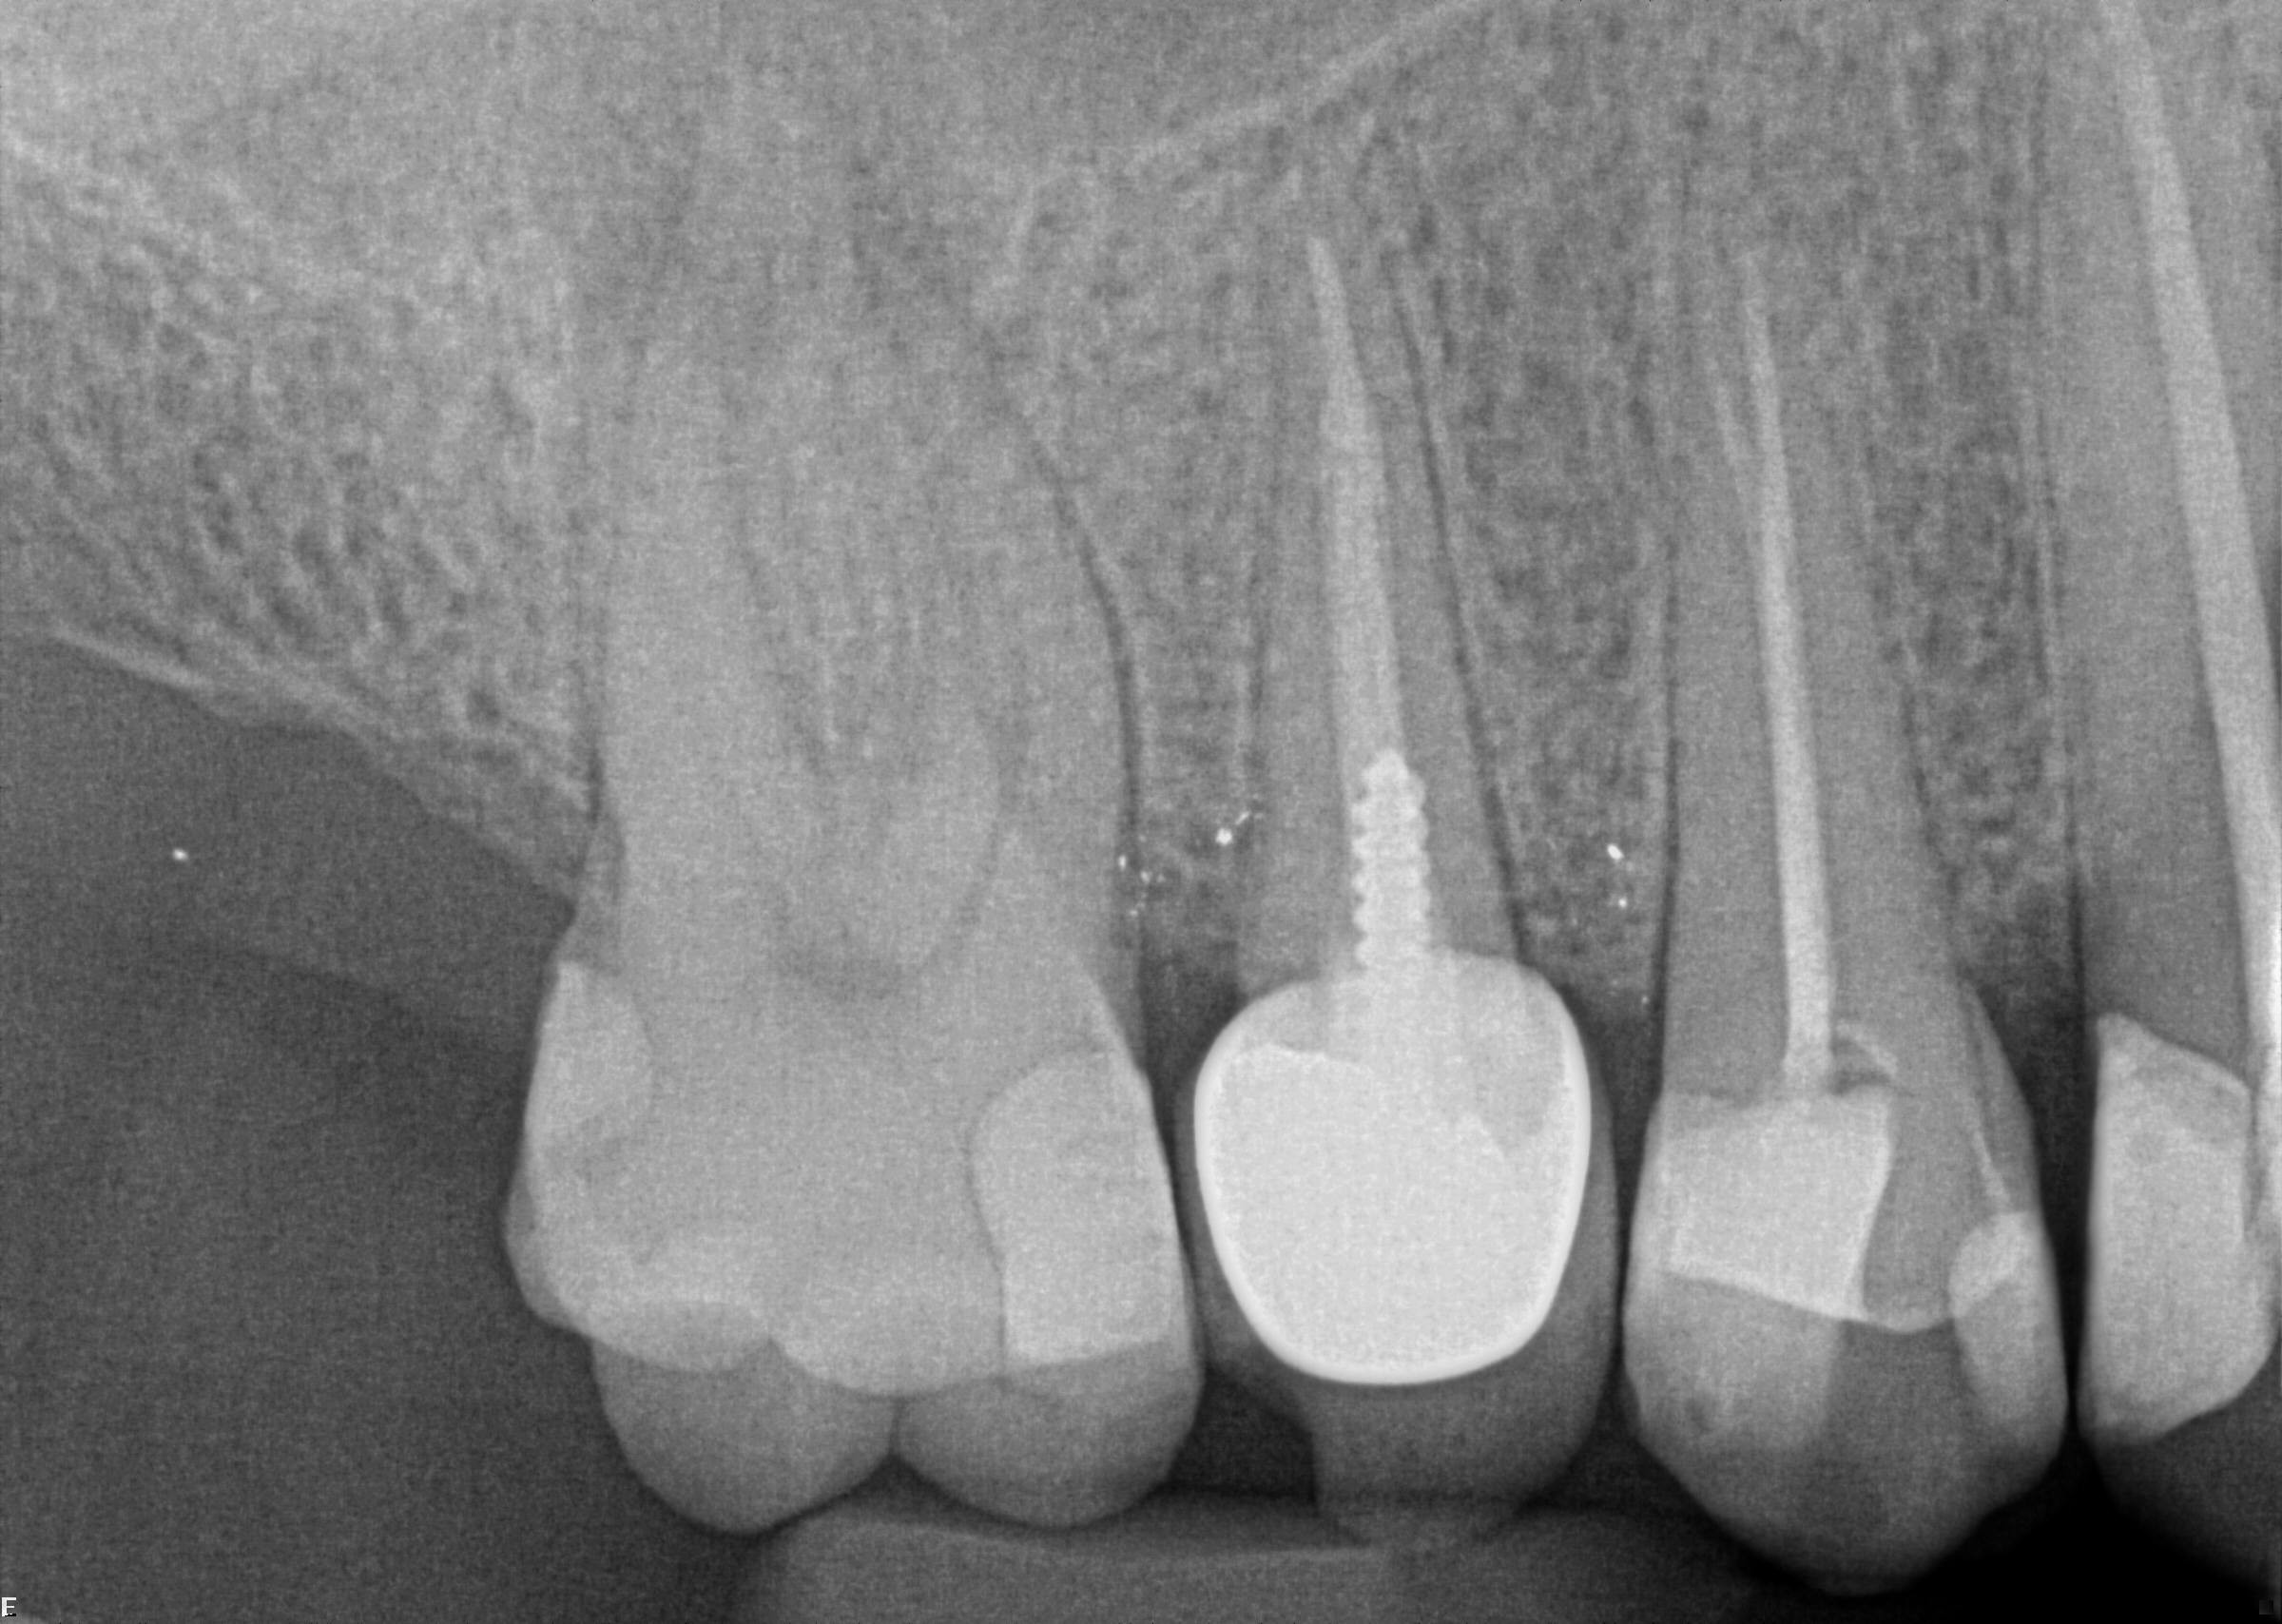

19. (Select ONE correct answer)

Regarding dental implant at site 3.6, there is evidence of

20. (Select ONE correct answer)

The radiograph shows evidence of